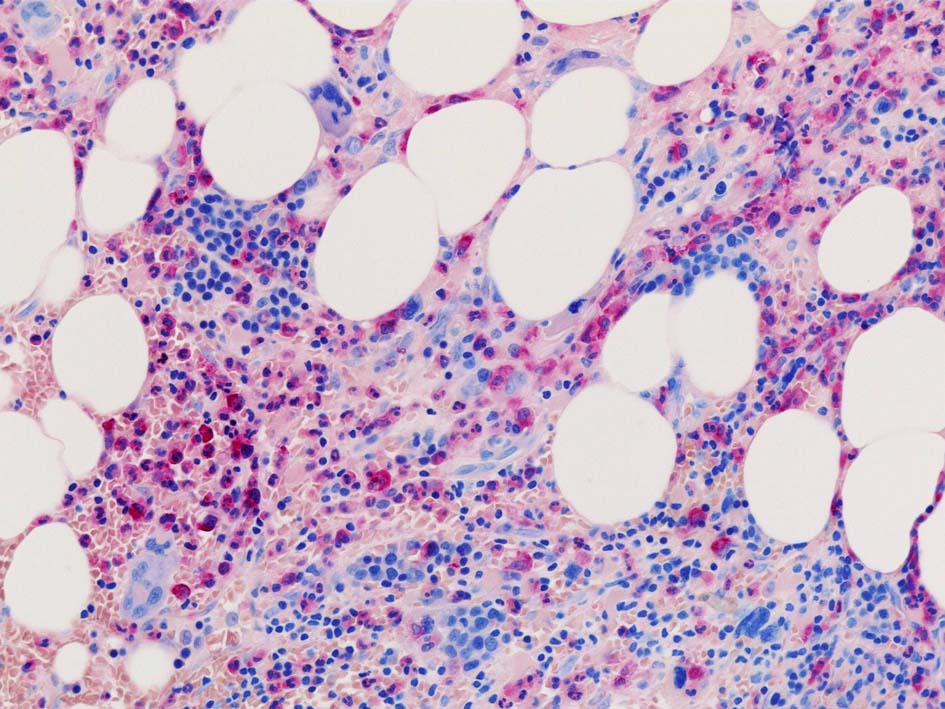

Case02; Meylofibrosis, overt fibrosis

77year-old female. 40歳時polycythemia veraと診断されていた.

黒染する弾性線維の増生のほか, 赤く染まる膠原線維の増生が確認される. MF-2 fibrosis. 鍍銀染色の核染色をすると膠原線維の赤染がわからなくなるので行わない.